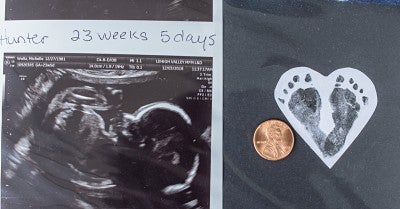

Michelle gave birth to their third son, Hunter, at just 24 weeks old. He was about the size of a Barbie doll, weighing 454 grams (1 pound) at birth. Hunter was so tiny that his first blood pressure cuffs fit on his mother’s pinky finger.

In terms of weight, Hunter was the smallest baby that neonatologist Linda Roberts, MD, with Lehigh Valley Reilly Children’s Hospital, had delivered to date.